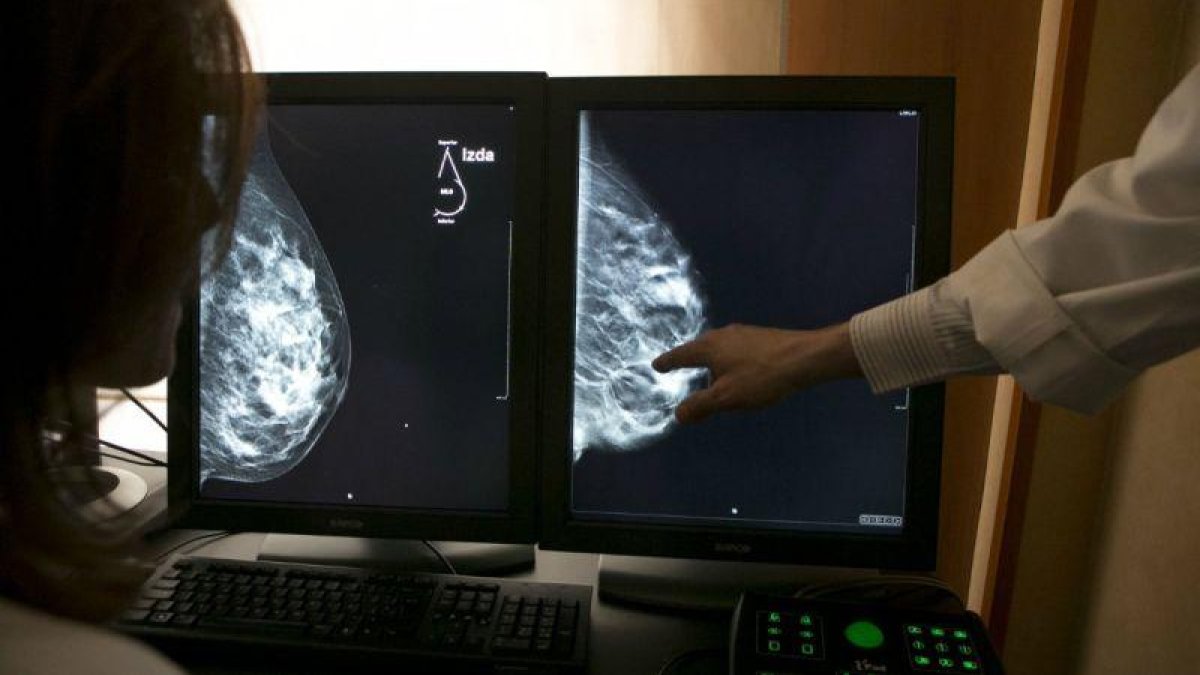

Imagen de archivo de una mamografía en 3D, que permite mejorar la detección del cáncer de mama.